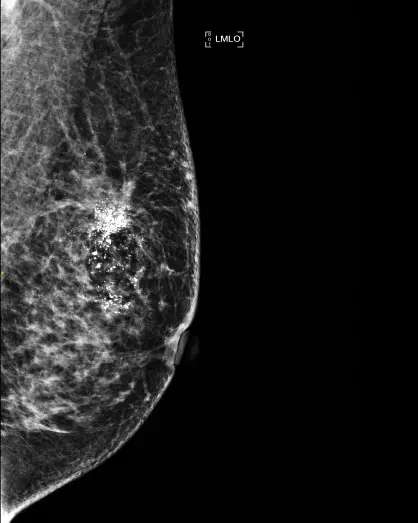

在钼靶的报告单上,钙化应该是最常见的描述性语言。钼靶片子就像一张乳房的黑白照片,钙化就是看到的乳腺里白色的小点(见图1,2),不要见到钙化就以为是恶性的,其实多数钙化还是良性的。

(图1,钼靶上的良性钙化)

根据钙化的形态和分布特征可以分为良性和恶性钙化,如散在的点状钙化,孤立的,粗大的,圆圆的钙化是良性的,而集群样,针尖,多形性的钙化有可能是恶性的。